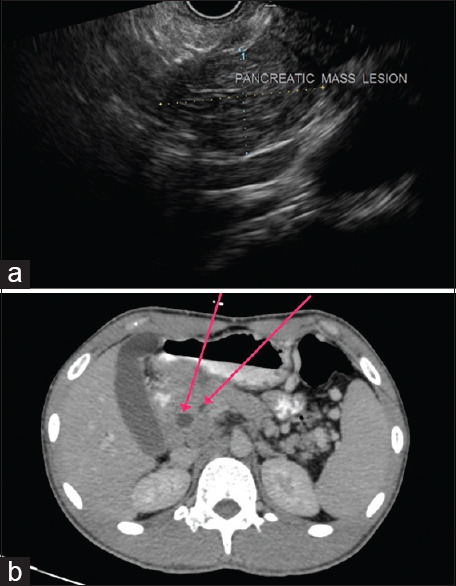

我们描述了一名患者,他在局部创伤后出现阴囊肿胀,随后阴囊窦不愈合并排出,最初被怀疑有感染性阴囊血肿。评估显示是阴囊结核。他还抱怨上腹部疼痛,经腹部超声检查发现胰头有肿块。胰腺肿块的评估显示是胰腺结核。两种病变对抗结核治疗反应良好。这是一个罕见的肺外结核两个罕见部位同时出现在同一个人身上的病例。在结核病流行国家,在评估任何无法愈合的溃疡、鼻窦和肿块时,都需要小心,因为这种疾病可能是一种很好的伪装。

We describe a patient who presented with scrotal swelling followed by non-healing and discharging scrotal sinuses, following local trauma and was initially suspected to have an infected scrotal hematoma. An evaluation revealed it to be scrotal tuberculosis. He also complained of upper abdominal pain and on transabdominal ultrasonography was detected to have a mass in the head of the pancreas. Evaluation of the pancreatic mass revealed it to be pancreatic tuberculosis. Both lesions responded well to anti-tubercular therapy. This is an unusual case of two rare sites of extrapulmonary tuberculosis presenting simultaneously in the same individual. Care needs to be exercised while evaluating any non-healing ulcers or sinuses and mass lesions in countries endemic for tuberculosis as this disease can be a great masquerader.